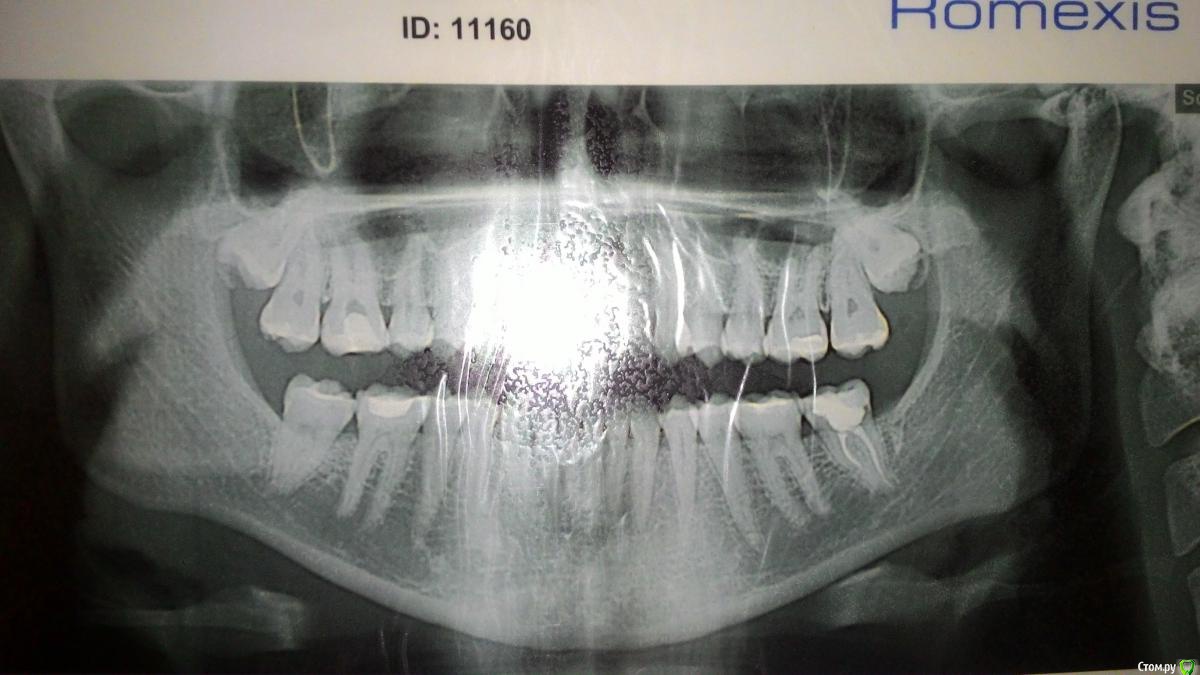

MargaritaM Опубликовано 29 октября, 2016 Поделиться Опубликовано 29 октября, 2016 Здравствуйте! Помогите, пожалуйста, советом, куда идти и что делать. С декабря 2013 года наблюдаюсь на Вучетича у профессора-хирурга (ЧЛХ). Диагноз: ретинированные верхние восьмерки, правая с зубосодержащей кистой. Хирург отказывается удалять, так как не видит хирургических причин удалять. На тему кисты говорит, что ничего страшного, если не растет - с ней можно всю жизнь проходить. Также не хочет удалять, т.к. с высокой вероятностью будет свищ, перфорация в пазуху. Делали ЭОД, хирург указал, что ноющая боль вызвана правой верхней шестеркой. Терапевт говорила, что всё с ней хорошо, но так как года 3 постоянно на нее жаловалась, удалили нерв. Удаление произошло не без приключений: заложили девитпасту на неделю, через 3 дня после заложения пасты адская боль, ее коллега удалила нерв (гноя, запаха не было, нерв не "рвался"), боль держалась, оставили зуб без пломбы на 2 дня, потом закладывали лекарство еще на 2 дня и прописали антибиотики. Боль постепенно стихала, но держалась. Дырку заделали пломбой. Сделали снимок - все каналы заделаны хорошо. После постановки пломбы зуб ныл около 2х недель. До сих пор периодичеки шестерка ныла, особенно когда простужалась или сильно нервничала. Сейчас есть как 4й день ноющая нестихающая боль в области между правой восьмеркой и шестеркой, с усилением ближе к ночи. Первые 3 дня ныла незначительно, сейчас уже сильнее. Есть ощущение, что десна немного припухла, цвет розовый, как у десны около других зубов. Подскажите, пожалуйста, шаг действий и куда еще можно обратиться на тему консультации с дальнейшим лечением/удалением.Пока записалась на прием к другому стоматологу-терапевту на консультацию на 2 ноября. Но сегодня 29 октября, как бы за 4 суток не стало поздно Ссылка на комментарий

kramer Опубликовано 29 октября, 2016 Поделиться Опубликовано 29 октября, 2016 Я бы удалил обе 8ки. Риск перфорации есть всегда, но это управляемо - можно же пластику сделать, ушить. Далее разбираться с 6 зубом. 1 Ссылка на комментарий

kladoffka Опубликовано 30 октября, 2016 Поделиться Опубликовано 30 октября, 2016 Вообще сложностей не увидел в обоих зубах. 2 Ссылка на комментарий

Kazankov.Egor Опубликовано 30 октября, 2016 Поделиться Опубликовано 30 октября, 2016 Кт верхней челюсти сделать нужно, сложности в удалении зубов нет, перфорация верхнечелюстной пазухи - рутинная амбулаторная процедура, решается за 20 минут.Не понятно что будет искать ЛОР. Ссылка на комментарий